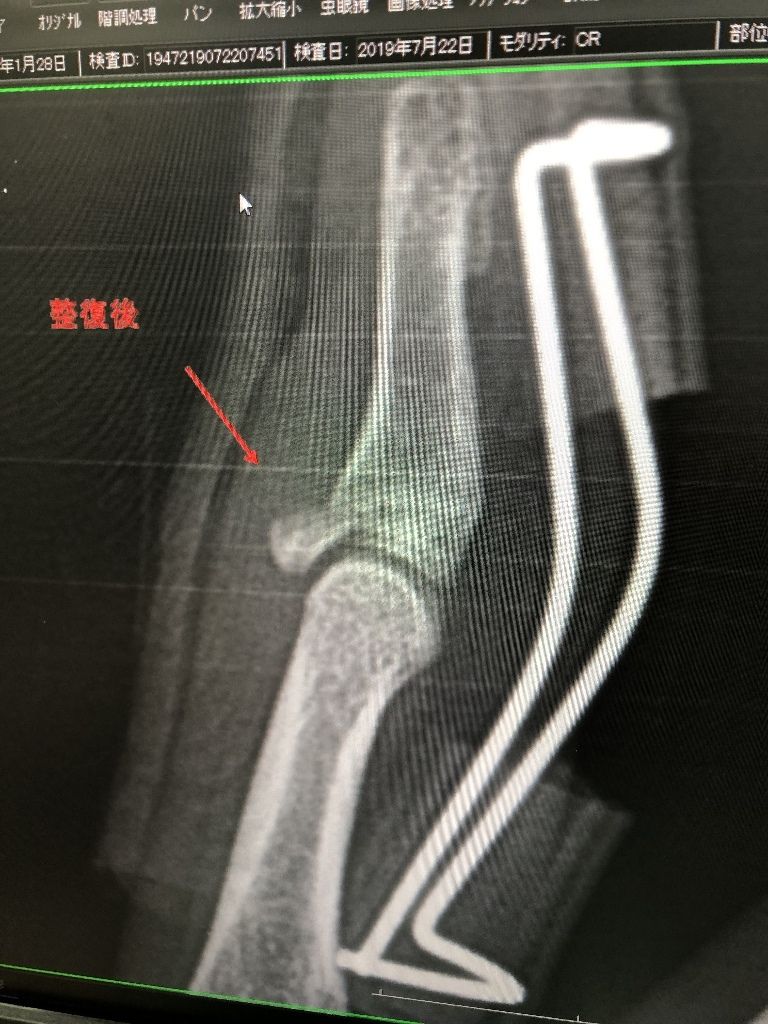

都市対抗野球試合が

盛り上がってきました!

4番スラッカーが骨折

イメージ 1

イメージ 2

本人、トレーナーの強い希望で

テーピングさせて、出場

センター前へ、ヒット

試合終わって 整復固定!

イメージ 3

本当にお疲れ様でした!